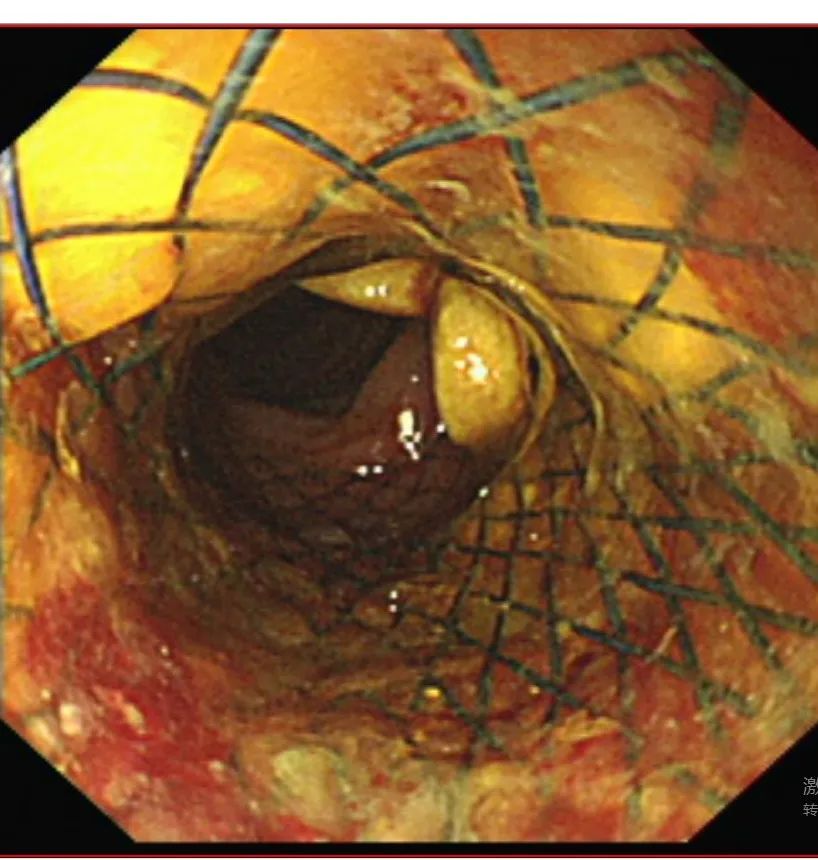

经过充分的术前准备,叶浩团队成功通过内镜将一枚金属支架精准放置到了患者的肠道梗阻部位,顺利撑开了狭窄的肠腔,瞬间“生命通道”被打通。整个手术过程微创、无痛,患者仅仅“睡了一觉”,醒来后腹痛、腹胀、呕吐等症状便消失了,术后即可进食流质饮食。患者和家属对治疗效果非常满意。

置入结肠金属支架,打通通道